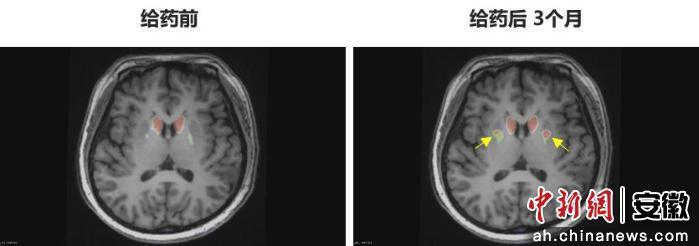

“身體不僵硬了,像正常人一樣?!崩钆啃χ?zhù)說(shuō)。多年的抖動(dòng)與“關(guān)期”徹底消失,她重新感受到身體的輕盈和心靈的自由。術(shù)后影像顯示,移植細胞已在腦內成功定植并發(fā)揮功能,醫生稱(chēng)這些“亮點(diǎn)”是新生多巴胺能神經(jīng)元的直接證據。

圖為李女士 PET-DAT/MRI融合圖像術(shù)前與術(shù)后三個(gè)月對比。

圖為李女士?PET-DAT/MRI融合圖像術(shù)前與術(shù)后三個(gè)月對比。